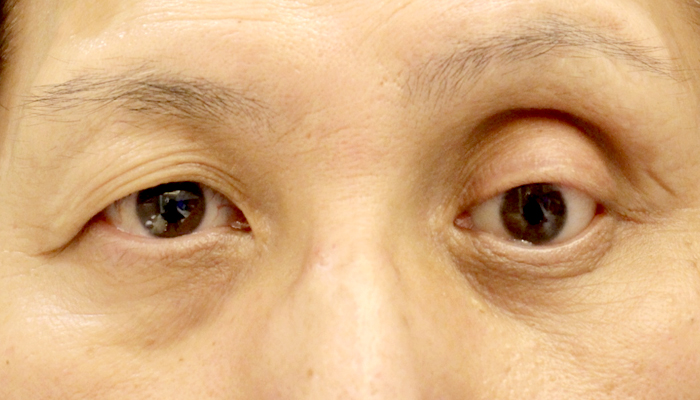

症例1

| 術前 | 左義眼、眼球陥凹 |

|---|---|

| 術後 | 左義眼台包埋、左上眼瞼下垂手術、左下眼瞼下垂手術 |

| 治療費 | 準備中 |

| 治療のリスク | 腫れが引かない、内出血がある、目が閉じにくい、完全に閉じないなどのリスクがあります |